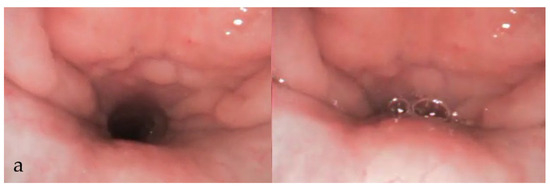

3.3. During DISE (Figure 1)

3.3.8. Documentation